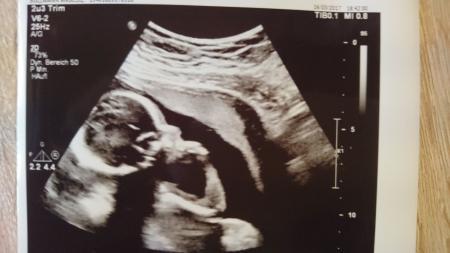

Heute war großer Ultraschall. Dem Knirps geht es gut, aber es wollte beim besten Willen nicht preisgeben obs Junge oder Mädchen ist :( In 2 Wochen lassen wir deswegen noch ein Ultraschall machen. Dafür gabs ein tolles Foto

Bild zu Auch zurück vom Frauenarzt - Forum für August - Mamis